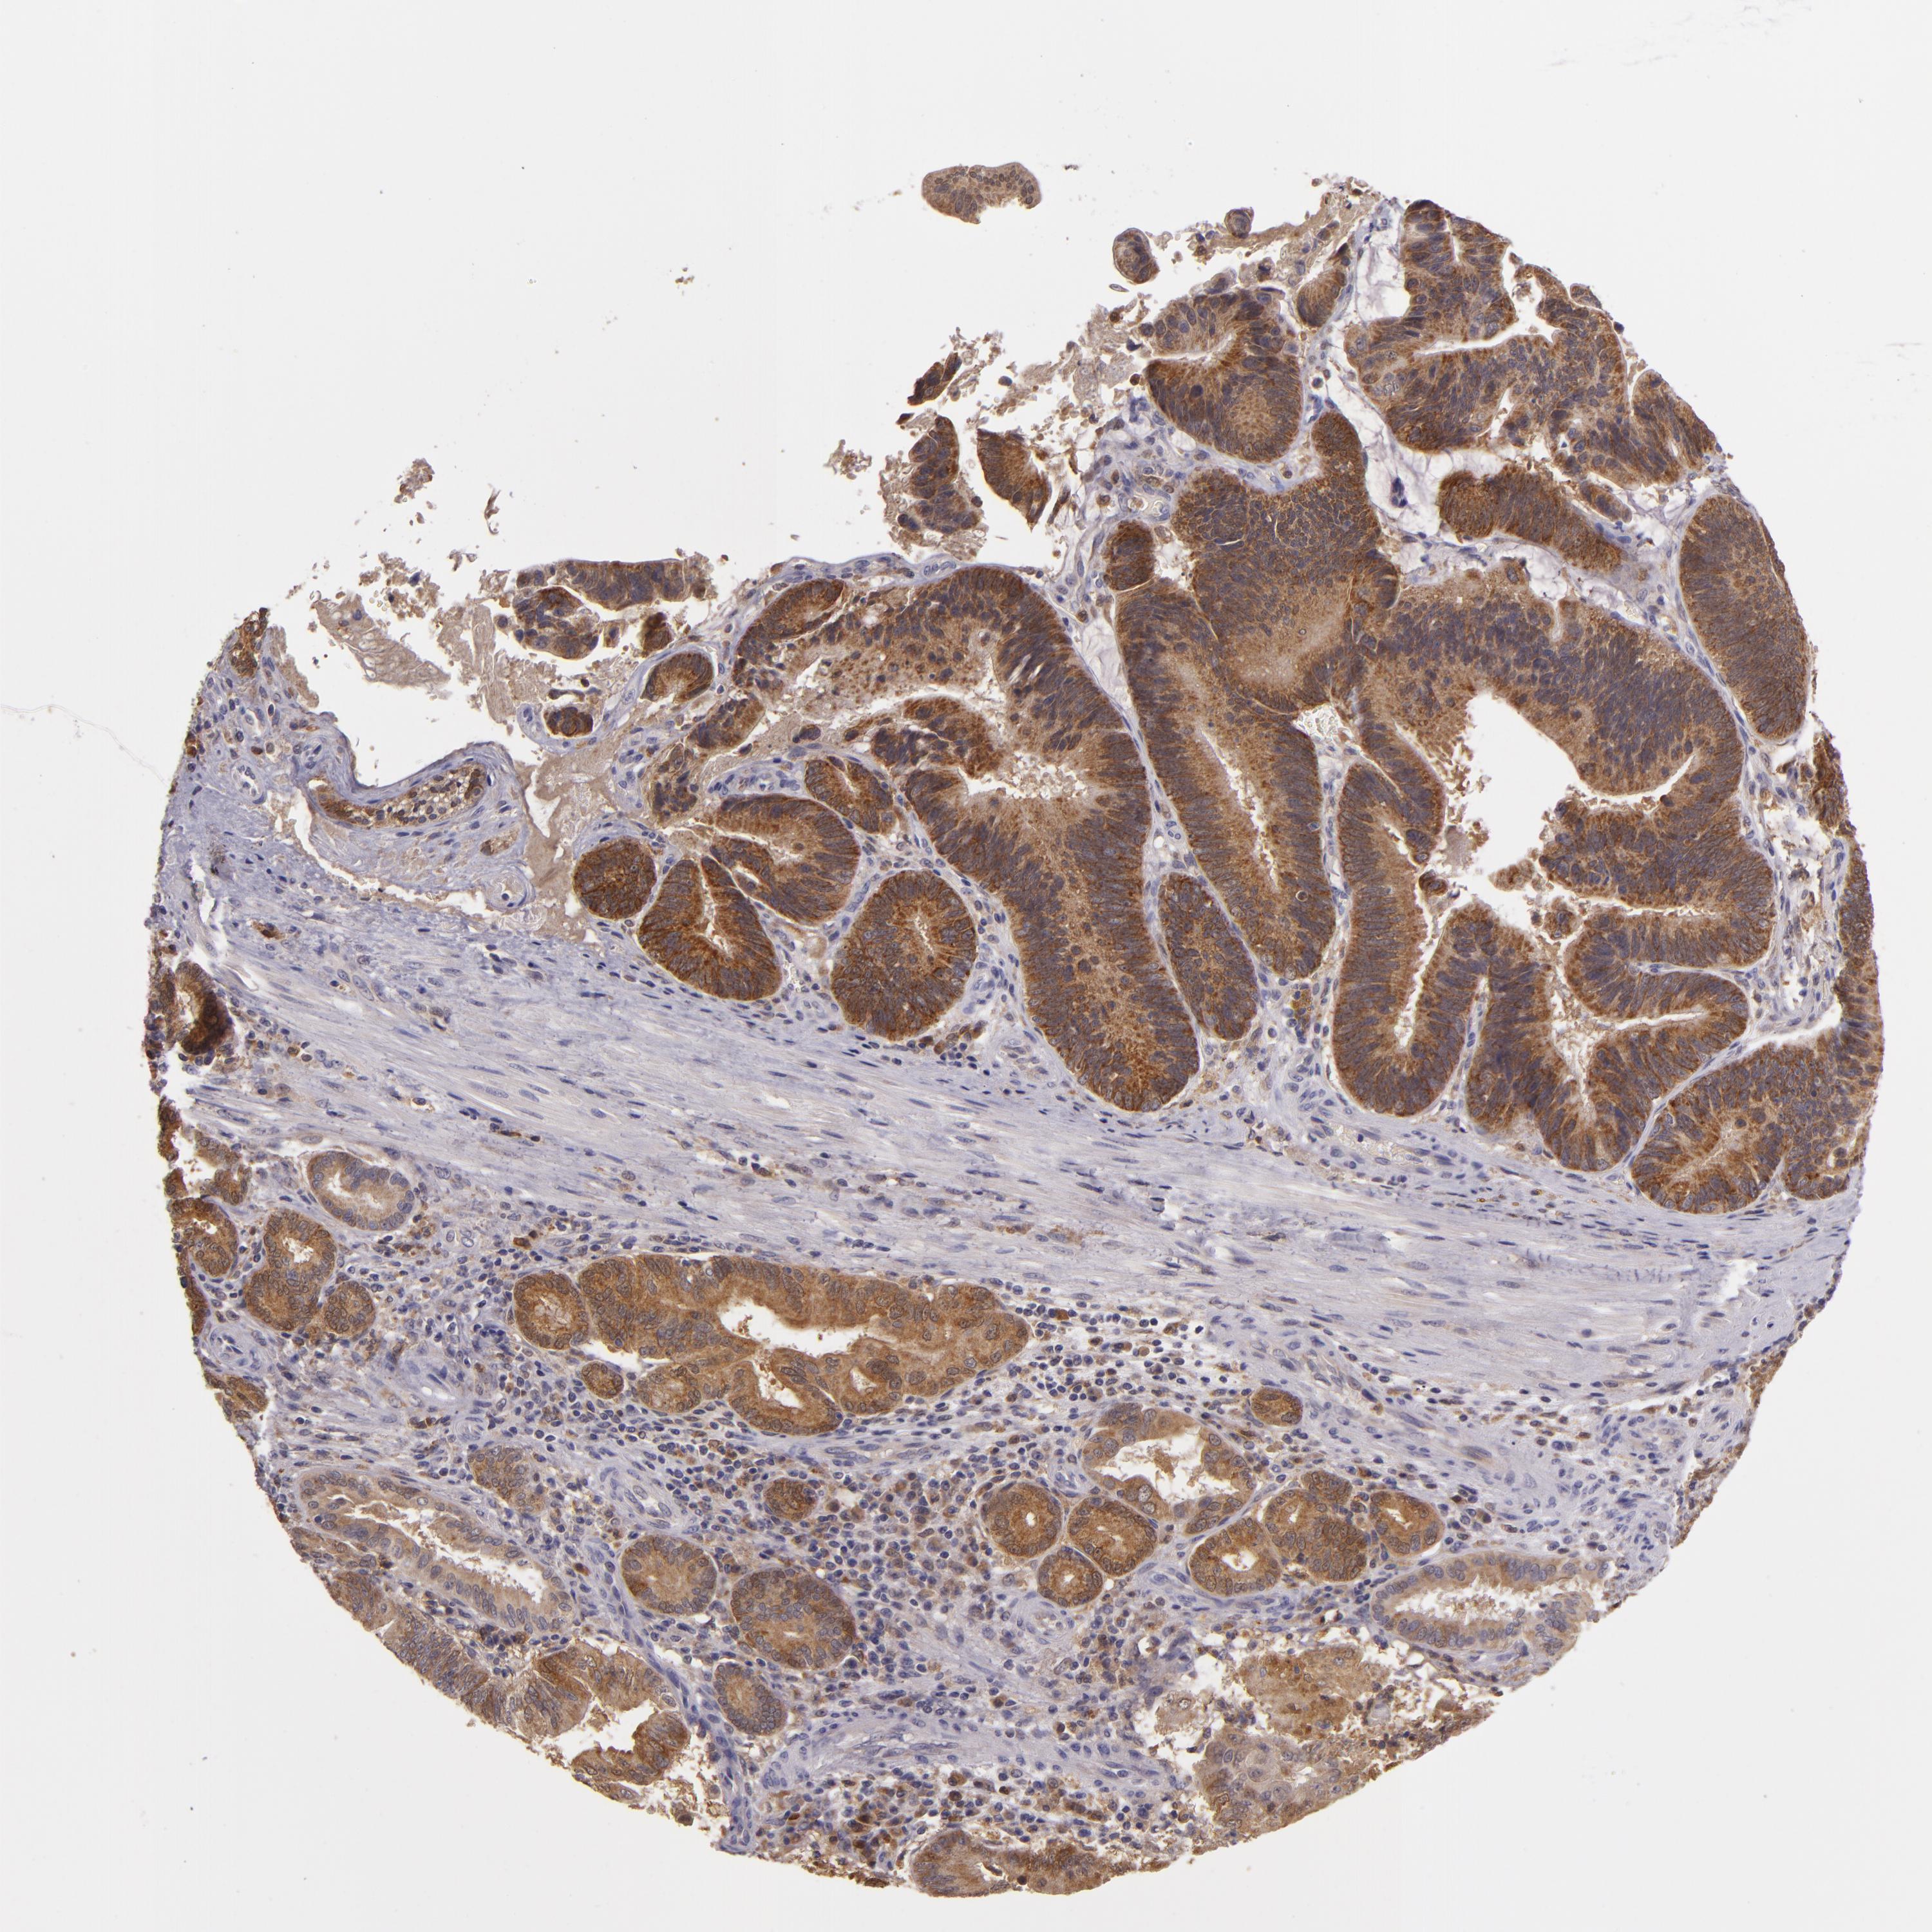

PANCREATIC CANCER - Protein expressioni

A mouse-over function shows sample information and annotation data. Click on an image to view it in a full screen mode. Samples can be filtered based on level of antibody staining by selecting one or several of the following categories: high, medium, low and not detected. The assay and annotation is described here.

Note that samples used for immunohistochemistry by the Human Protein Atlas do not correspond to samples in the TCGA dataset.

Antibody stainingi

Antibody staining in the annotated cell types in the current human tissue is reported as not detected, low, medium, or high, based on conventional immunohistochemistry profiling in selected tissues. This score is based on the combination of the staining intensity and fraction of stained cells.

Each image is clickable and will lead to virtual microscopy that enables deeper exploration of all samples and also displays staining intensity scores, fraction scores and subcellular localization as well as patient and tissue information for each sample.

Antibody HPA018840

Antibody HPA018909

Antibody CAB002684

Staining

High

Medium

Low

Not detected

Intensity

Strong

Moderate

Weak

Negative

Quantity

>75%

75%-25%

<25%

None

Location

Nuclear

Cytoplasmic/membranous

Cytoplasmic/membranous,nuclear

Adenocarcinoma, NOS

Adenocarcinoma, metastatic, NOS